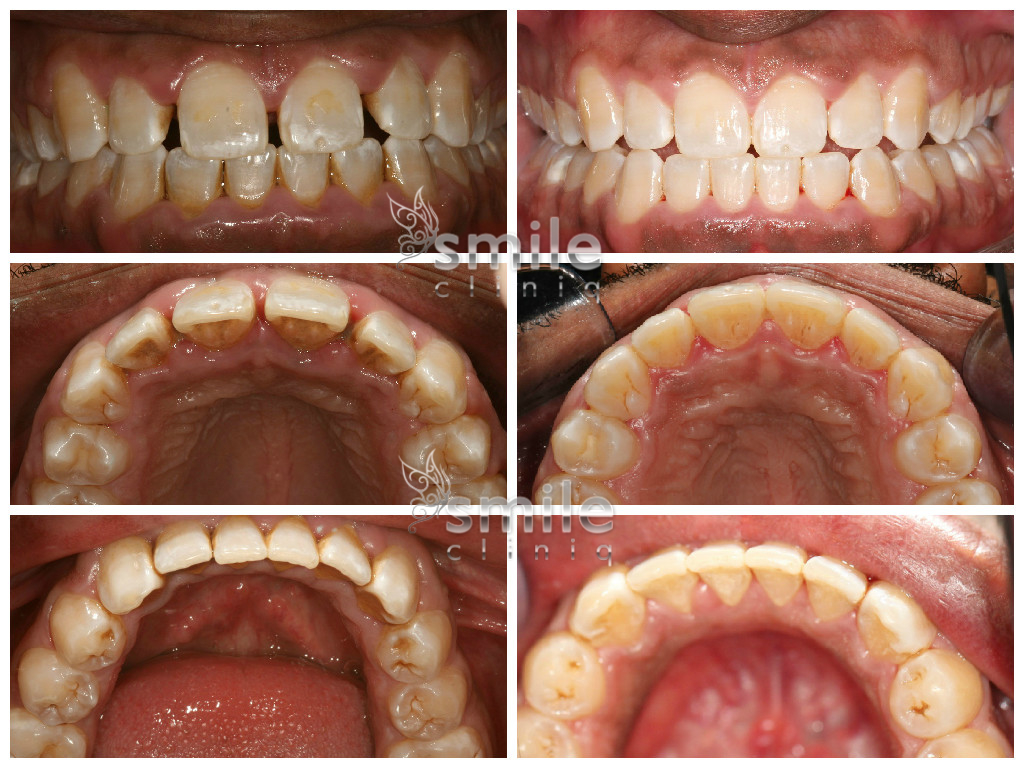

London Dentist Invisalign Before

Before

London Dentist Invisalign After

After

Please scroll below for some of our past Invisalign cases: